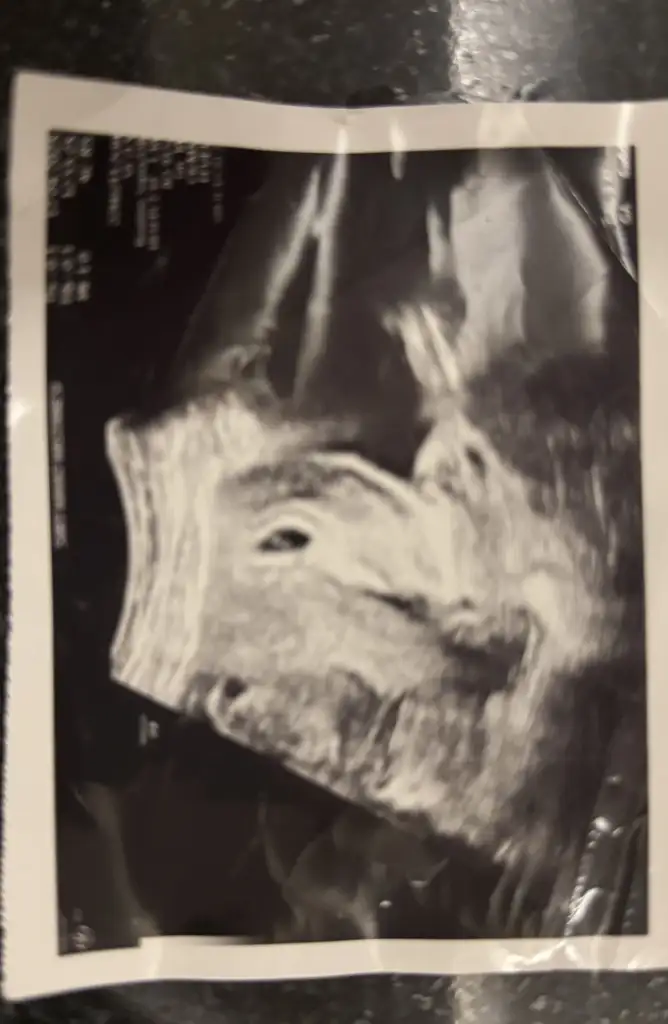

Merhaba karından ultrason 12 haftalık benim içinde yorum yaparsanız cinsiyetle alakalı çok sevinirim